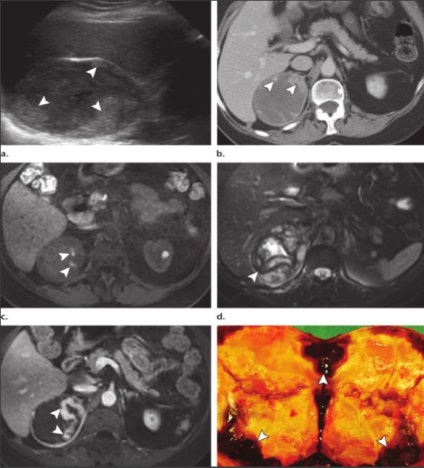

ADENOM BARK NADPOCHENCHIKOV.

- Adenom - cea mai frecventă tumoră n. cu 1,4 8,9% din totalul autopsiilor.

- unenhanced CT: densitate 10 HU este vysokuyuchuvstvitelnost (79%) și specificitate (96%).

MR modificări de schimbare chimică utilizează frecvențe diferite precesional de protoni în apă față de protoni grăsime din cadrul aceluiași voxel și creează în fază și în afara faze de imagine în care un semnal de protoni sunt însumate sau scăzute unul de altul. Această secvență evaluează grăsime intracitoplasmatică găsite în cele mai multe adenoamelor. Cele mai multe adenoame arată o scădere a intensității semnalului în imagini de fază distincte.

ADENOM BARK NADPOCHENCHIKOV.

10% -40% au puțină grăsime (≥10HU), astfel adenoamelor numita "lipid-săraci" și sunt considerate nesigure, este opacifierea necesar (după 1 min și 15 min).